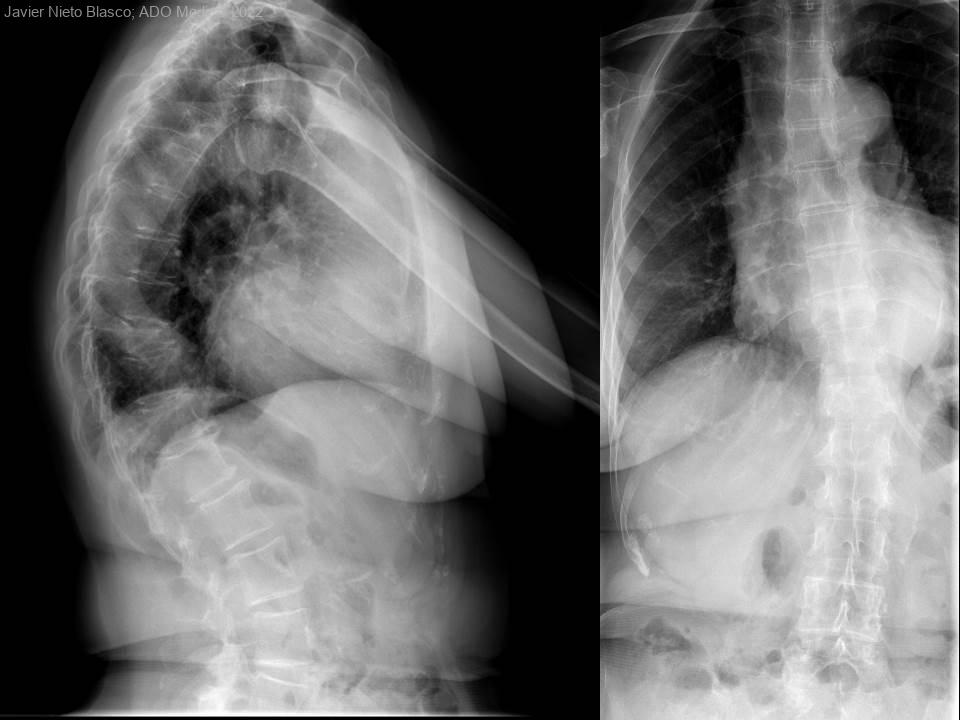

¿Es el ictus una causa de osteoporosis y fractura?. A propósito de un caso

Mujer de 66 años, sin antecedentes de fracturas previas ni alteraciones metabólicas óseas conocidas, con ACV hemorrágico, con hemiparesia derecha espástica, dependiente parcial para las actividades de la vida diaria, que realiza marcha independiente en...